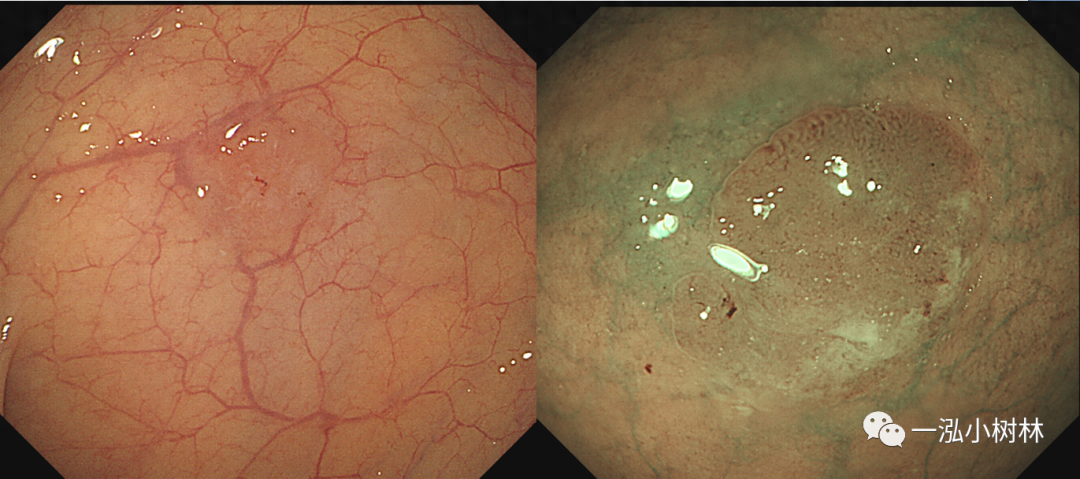

图4 结肠管状腺瘤(Pit Pattern IIIS+IIIL型)